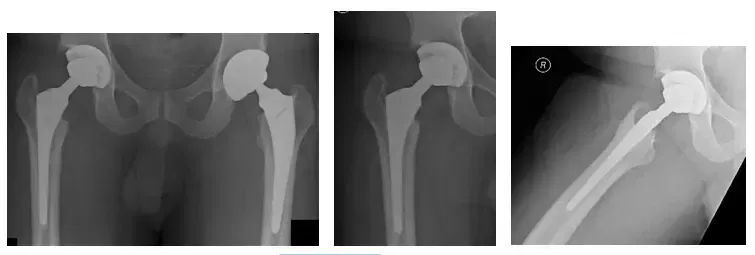

Las radiografías muestran una prótesis total de cadera derecha con lucencia alrededor del componente acetabular

Las radiografías muestran una revisión total de la cadera derecha durante la operación. La prótesis está bien colocada

Las radiografías a los seis meses del postoperatorio muestran la prótesis en buena posición